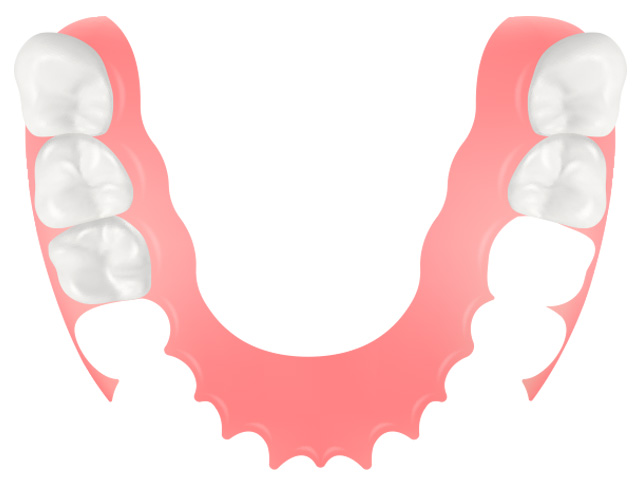

では、下のような患者様はどうでしょうか?

上の歯は前歯を中心に失っているのに対し、下の歯は奥歯を中心に失っています。このような場合を「すれ違い咬合」といって、入れ歯を作っても天然の歯による支持が不足することになるため、うまくいきません。

この場合は、インプラントを適切に配置することで、「すれ違い」を回避すれば、入れ歯を作りやすくすることが可能です。

このように、患者様ごとに難易度が異なり、それをしっかりと把握して対処する必要があります。